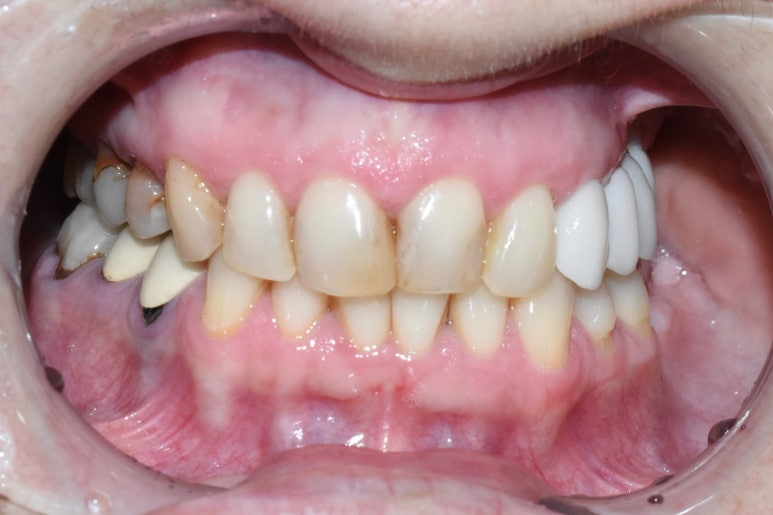

치료 전

(치료전) 환자분 나라에서 한 임플란트 크라운과 치아색이 너무 차이가 났습니다.

(치료전) 앞니가 이쁜 편이 아니라 색도 모양도 바꾸고 싶어 하셨어요.

또한 임플란트가 오른쪽이라면 반대쪽인 왼쪽 치아들은 신경치료 후에 크라운을 하지 않아

치아가 망가지고 있어서 사진상 윗니의 왼쪽 어금니 쪽은 크라운을 하기로 했습니다.